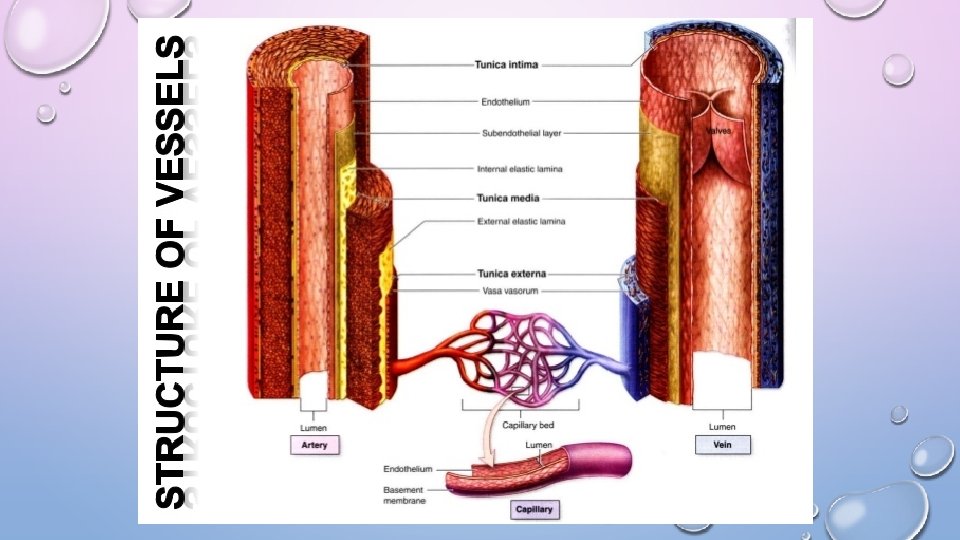

BLOOD VESSELS • NETWORK OF TUBES • ARTERIES → ARTERIOLES • MOVE AWAY FROM HEART, • ELASTIC FIBERS • SMOOTH CIRCULAR MUSCLES • VEINS → VENULES • MOVES TOWARD THE HEART • SKELETAL MUSCLE CONTRACTS TO FORCE BLOOD BACK FROM LEGS • 1 WAY VALVES • WHEN THEY BREAK → VARICOSE VEINS FORM

TINY, TINY VESSELS • CAPILLARIES- WHERE GAS EXCHANGE TAKES PLACE • 1 CELL THICK • SERVES RESPIRATORY SYSTEM • ARTERIOLES- MICROSCOPIC ARTERIES